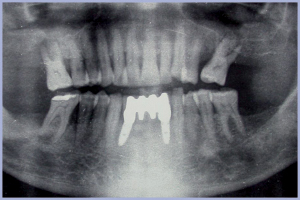

- Figg. 32, 33 – Settori sup. DX e SX: follow up radiografico a 3 anni dal carico

- Fig. 34 – Follow up radiologico a 5 anni dal carico. Notare l’eccellente mantenimento osseo marginale a livello degli impianti